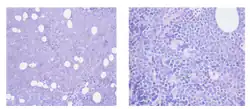

Adult Atypical Sporadic Burkitt Lymphoma successfully treated with Bendamustine and Rituximab